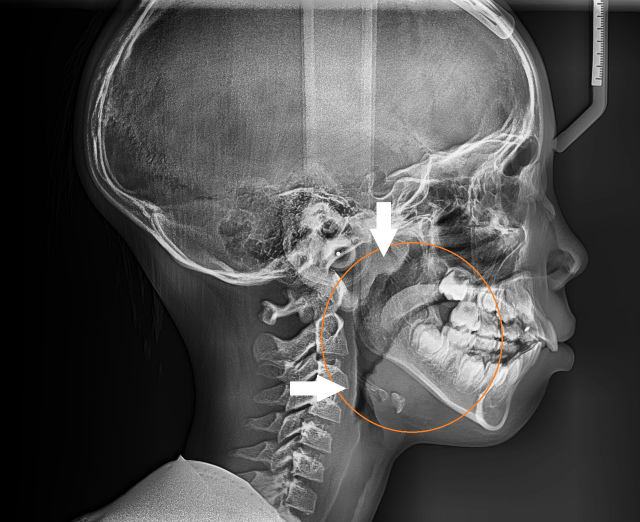

一番上の矢印は咽頭扁桃(アデノイド)が腫れている箇所を示している。気道が全域で狭くなっている (8歳男児)